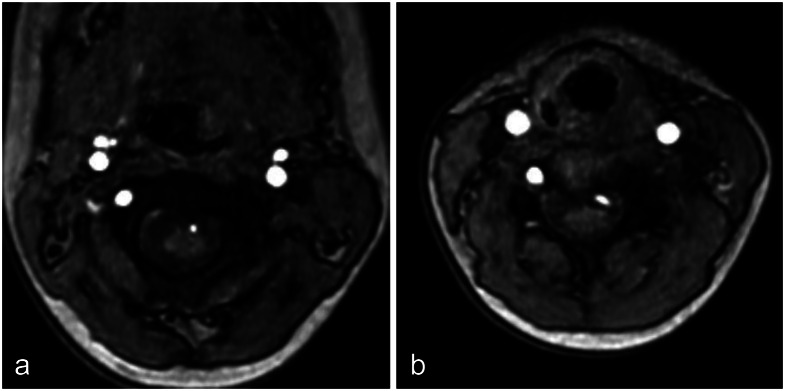

Purpose: The vertebral artery (VA) typically enters the subarachnoid space at the atlanto-occipital region. However, segmental variations can occur, with the VA entering the spinal canal at atypical levels. While a C3 segmental VA has been reported, no prior studies describe a C5 segmental VA. This case represents the first documented occurrence of this anomaly.

Methods: An 8-year-old girl underwent brain magnetic resonance imaging for headache screening, which incidentally revealed an abnormal VA course.

Results: Imaging revealed the absence of the left VA at the proximal V2 segment. Instead, a radiculomedullary artery at C4/5 entered the spinal canal and contributed to the formation of the anterior spinal artery (ASA), which ascended along the spinal cord. The right VA appeared normal; however, a radiculomedullary artery at the C3/4 level was identified, joining the contralateral radiculomedullary artery at the C1 level to form the ASA. Additionally, bilateral accessory middle cerebral arteries were observed. No clear association was found between this anomaly and the patient's headache, and she remained under observation.

Conclusion: This anomaly may result from persistence of the fifth intersegmental artery. The vascular course resembled collateral circulation observed in acquired VA occlusion. Given its proximity to the spinal cord, potential risks include ischemic complications and spinal cord compression. This case highlights the importance of accurate imaging and careful surgical planning. Further studies on these rare vascular anomalies will enhance our understanding of VA variations and their clinical significance.